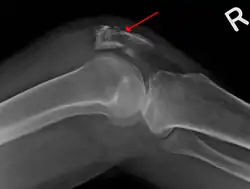

Osteochondral fracture of patella -